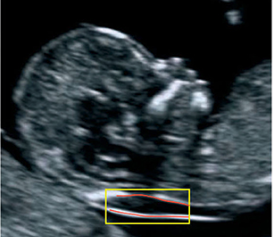

Fetal Medicine, Ontology design, Semantic reasoning

- Dhombres F, Bonnard J, Bailly K, Maurice P, Papageorghiou A, Jouannic JM. Contributions of artificial intelligence reported in Obstetrics and Gynecology journals: a systematic review. J Med Internet Res. 2022 Mar 15;. doi: 10.2196/35465. [Epub ahead of print] PubMed PMID: 35297766.